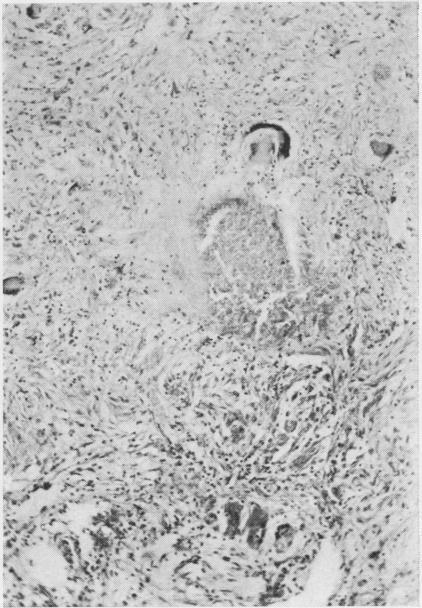

As is known, the inhalation of animal hairs can provoke immunological reactions in the respiratory tract affecting the naso-tracheo-bronchial sector and giving rise to asthma-like syndromes. Another form of disease, found in furriers with long exposure to hair dust', is described. It is characterized by a granulomatous interstitial pneumonia, of the tuberculoid type, very similar to that described in other diseases related to the inhalation of organic dusts, both vegetable and animal, such as farmer's lung' and `bird fancier's lung'. This new disease—which we experimentally reproduced—can be diagnosed from the occupational history together with the finding on lung biopsy of hair shafts within granulomatous lesions (birefringence and histo-chemical reactions). As in other diseases of this type, a host factor of probable immunological nature is suggested. Attention is drawn to the need to protect workers in the furrier's trade.